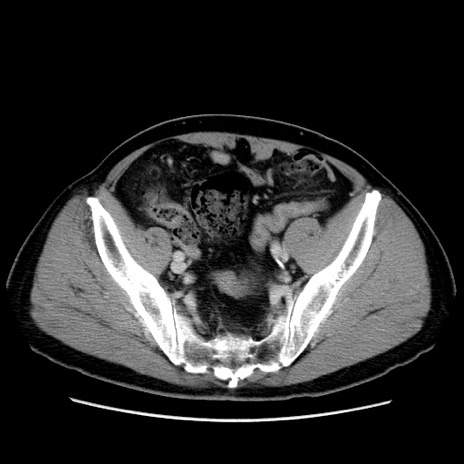

症例34(横断像)

【症例】60歳代 男性

【主訴】右鼠径部膨隆

【現病歴】1年程前より右鼠径部膨隆あり。自己にて還納可能だったため放置していた。3時間前より右鼠径部の脱出を認め、還納困難となり受診。

【既往歴】高血圧

【身体所見】右鼠径部に小児頭大の膨隆あり。弾性硬であり、用手還納は困難。左鼠径部にも膨隆を認める。脱出はなし。